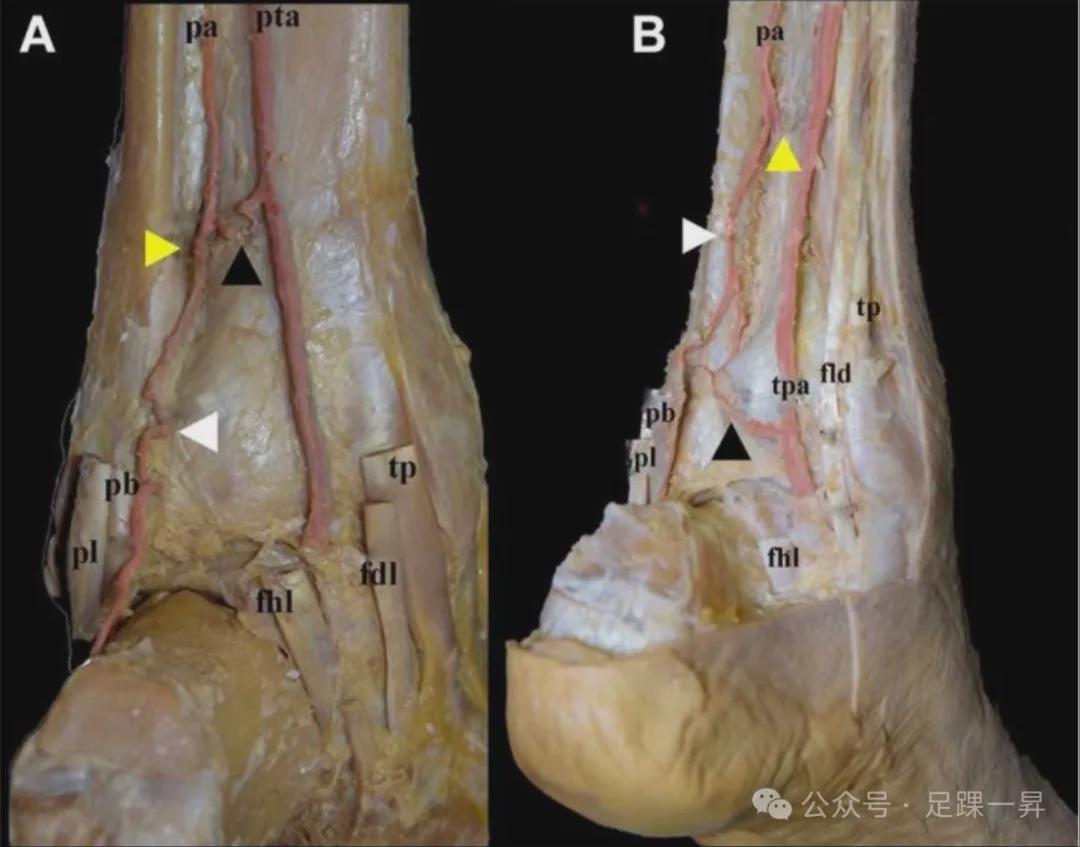

图 5:(A)小腿后部视图显示腓动脉(pa)终末三分,吻合支(黑色箭头)最终与后腓动脉(白色箭头)和胫后动脉吻合。(B)小腿后内侧视图显示 3B 型,即前穿支(黄色箭头)、吻合支(黑色箭头)和后腓动脉(白色箭头)。FDL 为趾长屈肌,FHL 为拇长屈肌,PB 为腓骨短肌,PL 为腓骨长肌,TN 为胫神经,TP 为胫后肌